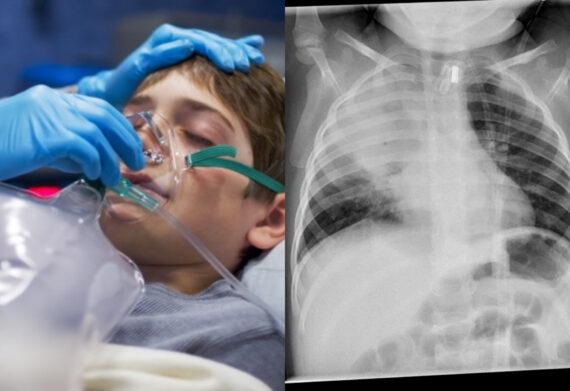

Μεγάλη είναι η διασπορά της γρίπης και τον εποχικών ιώσεων στα παιδιά αυτό το διάστημα. Ο Παιδίατρος Σπύρος Μαζάνης, μιλώντας το πρωί της Δευτέρας στο Newsbomb.gr αναφέρθηκε στις αναπνευστικές λοιμώξεις του χειμώνα που φέτος έχουν κάνει την εμφάνισή τους νωρίτερα αλλά και με μεγαλύτερη ένταση σε σχέση με προηγούμενες χρονιές.

Τις ιογενείς λοιμώξεις σε κάποιες περιπτώσεις ακολουθούν και οι βακτηριακές, με τους παιδιάτρους να βλέπουν αυτή την περίοδο πολλά περιστατικά πνευμονίας που προέρχονται από πνευμονιόκοκκο. Επιπλέον, οι ειδικοί συχνά συναντούν υποτροπές των ιώσεων, δηλαδή μία επόμενη φάση της ίδιας ίωσης, όπου ενώ έχει υποχωρήσει ο πυρετός επανέρχεται για ακόμα μια φορά.

«Υπάρχει μια έξαρση της νοσηρότητας αυτή τη στιγμή με μια αύξηση 20% κάθε εβδομάδα στις ιώσεις. Είναι τέτοια η έξαρση που στα νοσοκομεία έχουν γεμίσει τα κρεβάτια, είναι πολύ δύσκολο ένα άρρωστο παιδί να νοσηλευτεί αυτή τη στιγμή», ανέφερε αρχικά ο κ. Μαζάνης και εξήγησε τα χαρακτηριστικά της έξαρσης υπογραμμίζοντας ότι είναι τρία:

Αυτή την εποχή υπάρχουν πολλές διαφορετικές ιώσεις, οι οποίες έχουν τα ίδια συμπτώματα του αναπνευστικού συστήματος δηλαδή βήχα, πυρετό. ένα παιδί μπορεί ταυτόχρονα να έχει δυο και τρεις ιούς». Ποιες λοιμώξεις προκαλούνται από τον πνευμονιόκοκκο Ο ίδιος αναφέρθηκε και στον πνευμονιόκοκκο, το μικρόβιο που έρχεται αντιμέτωπο συχνά με το αναπνευστικό σύστημα παιδιών αλλά και ενηλίκων.

«Έχουμε πολλά περιστατικά από ένα μικρόβιο που λέγεται “πνευμονιόκοκκος” που κάνει πνευμονίες και φαίνεται ότι επειδή πολλά παιδιά έχουν καθυστερήσει τον εμβολιασμό ή δεν έχουν ολοκληρώσει τις αναμνηστικές δόσεις μέσα στην καραντίνα. Τα παιδιά είναι ευάλωτα και έτσι έχουμε πολλά περιστατικά νοσηρότητας με πνευμονιόκοκκο. Γι’ αυτό αν θέλουν οι γονείς σε ένα βαθμό να βοηθήσουν τα παιδιά τους πρέπει να κάνουν τα εμβόλια του πνευμονιόκοκκου και της γρίπης γιατί έχουμε πολλά περιστατικά με γρίπη», είπε μιλώντας στο Newsbomb.gr ο κ. Μαζάνης.